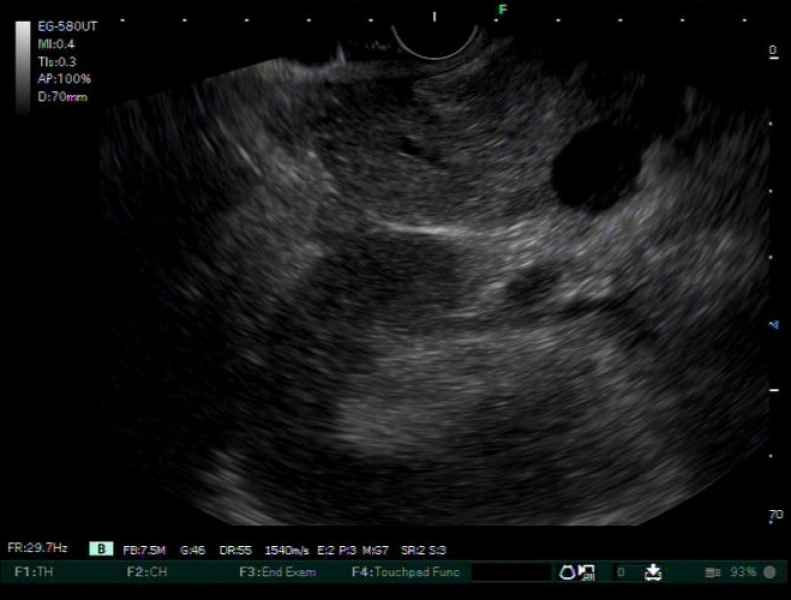

From IPMN to IPMN-derived invasive adenocarcinoma